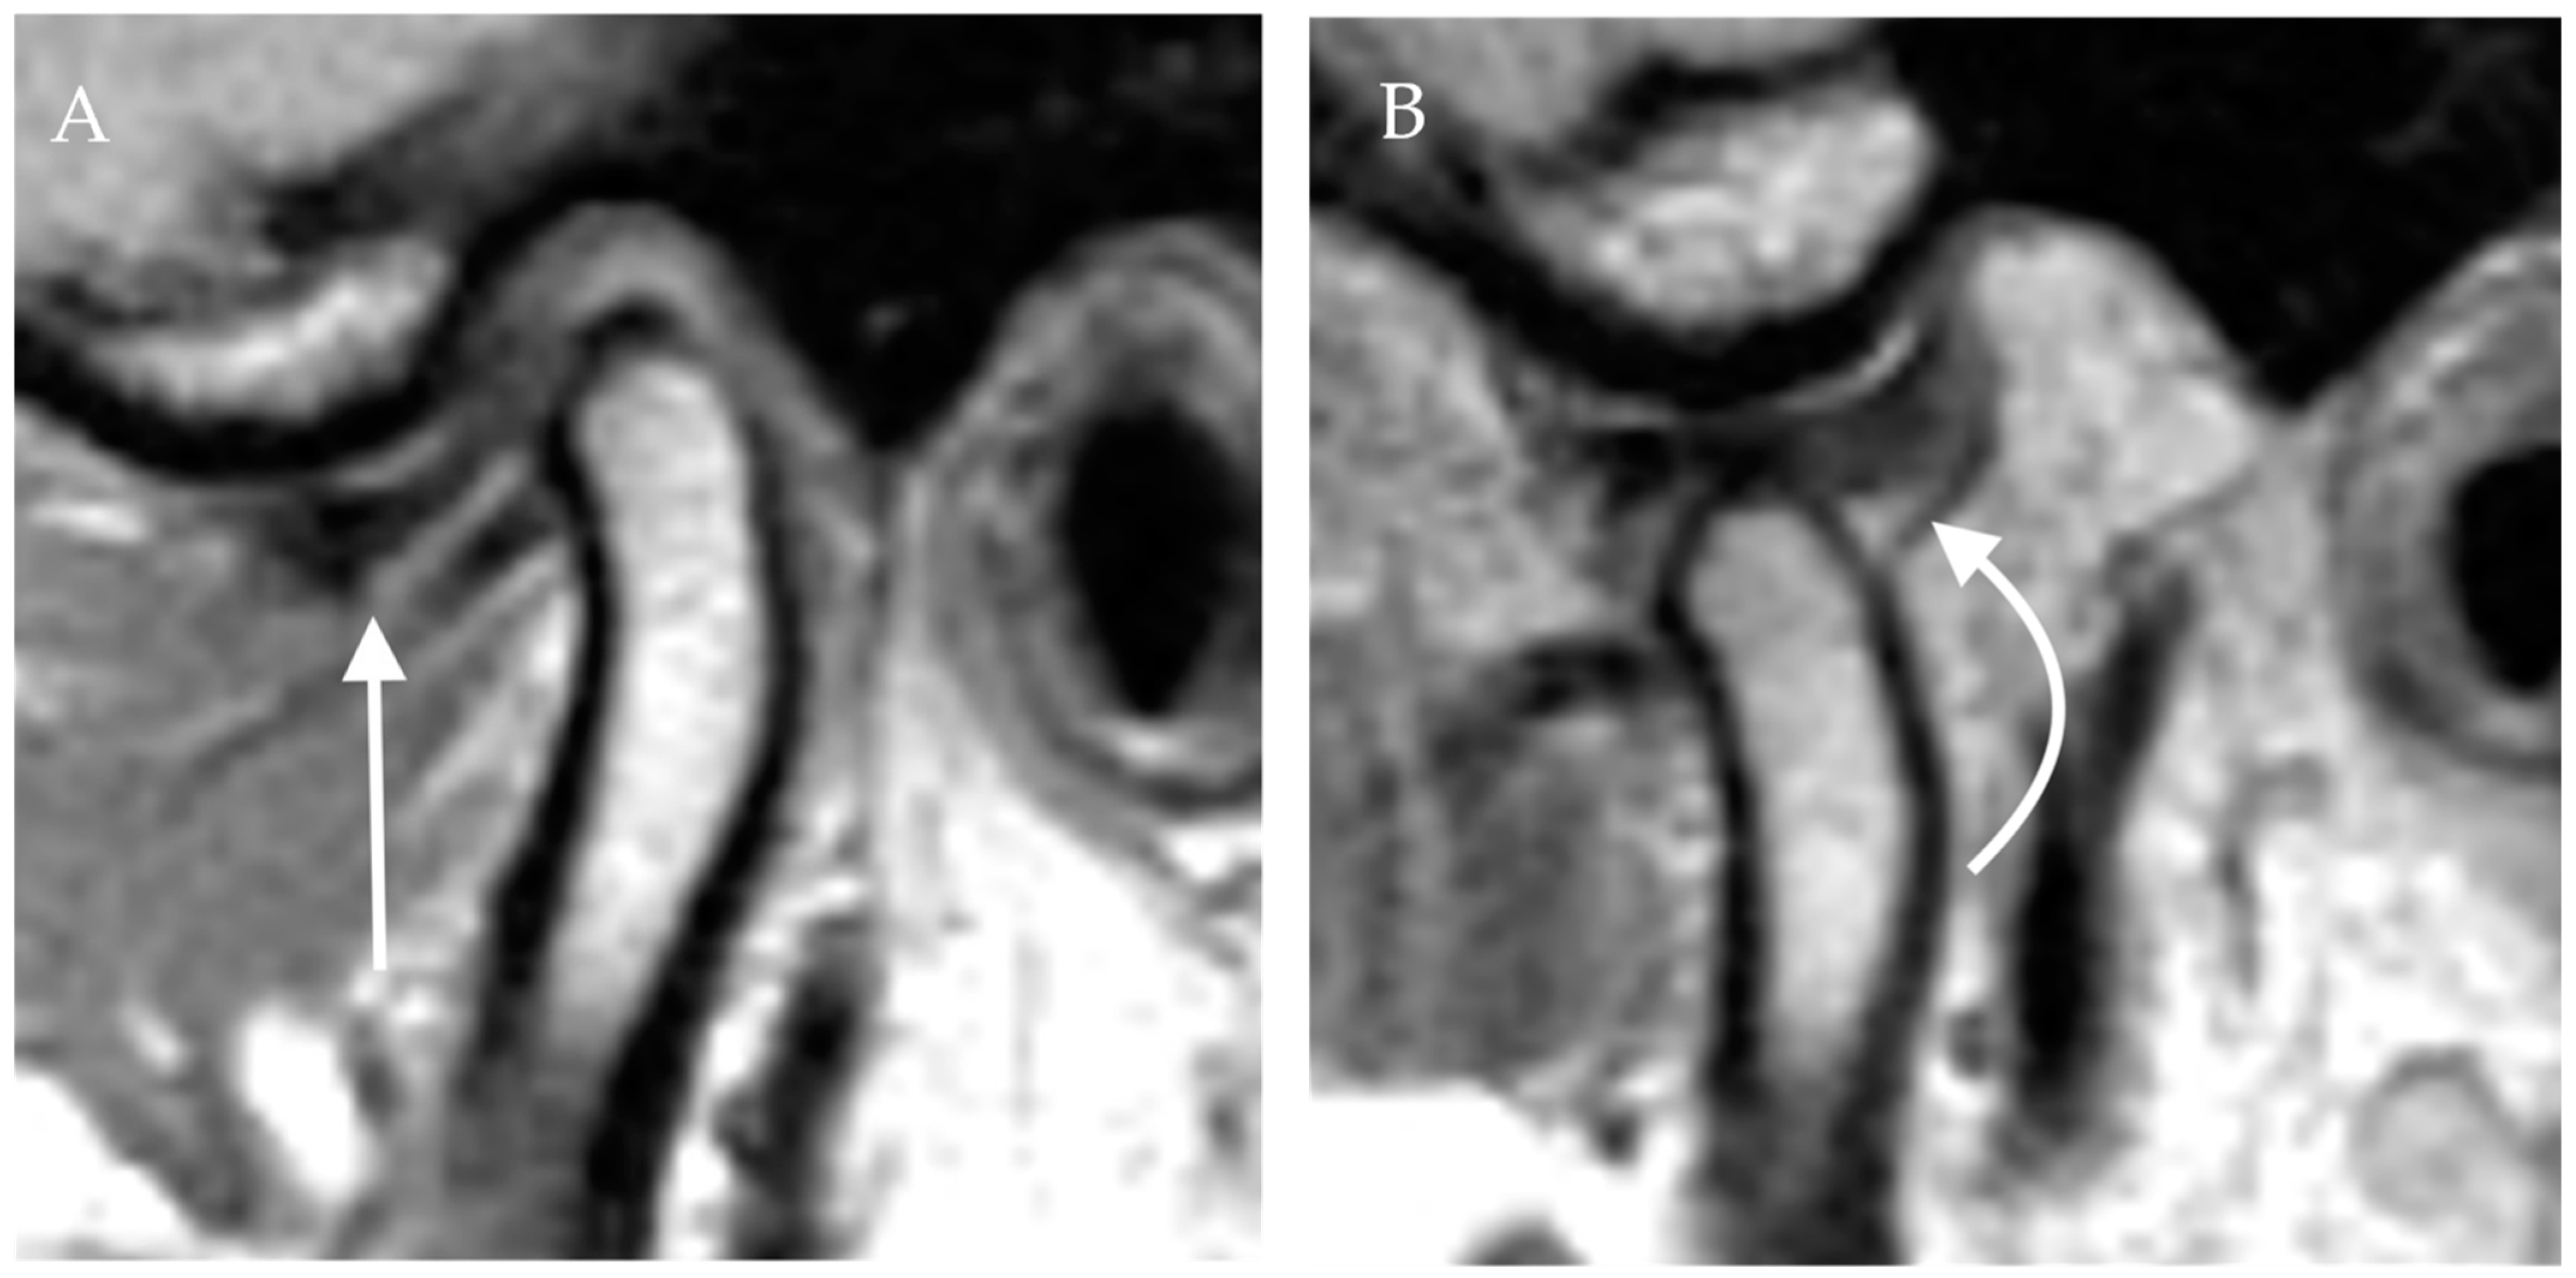

Figure 4. Anterior disc displacement with recapture. Proton density sagittal image of the TMJ in closed mouth (A) position shows anterior displacement of the articular disc with otherwise normal bow-tie appearance (straight arrow). The mandibular condyle is situated in an anatomic location within the mandibular fossa. On open mouth images (B), normal condylar rotation and anterior translation are noted. Note the recapture of the articular disc, which is now in the normal position (curved arrow). The bow-tie appearance of the articular disc is preserved.